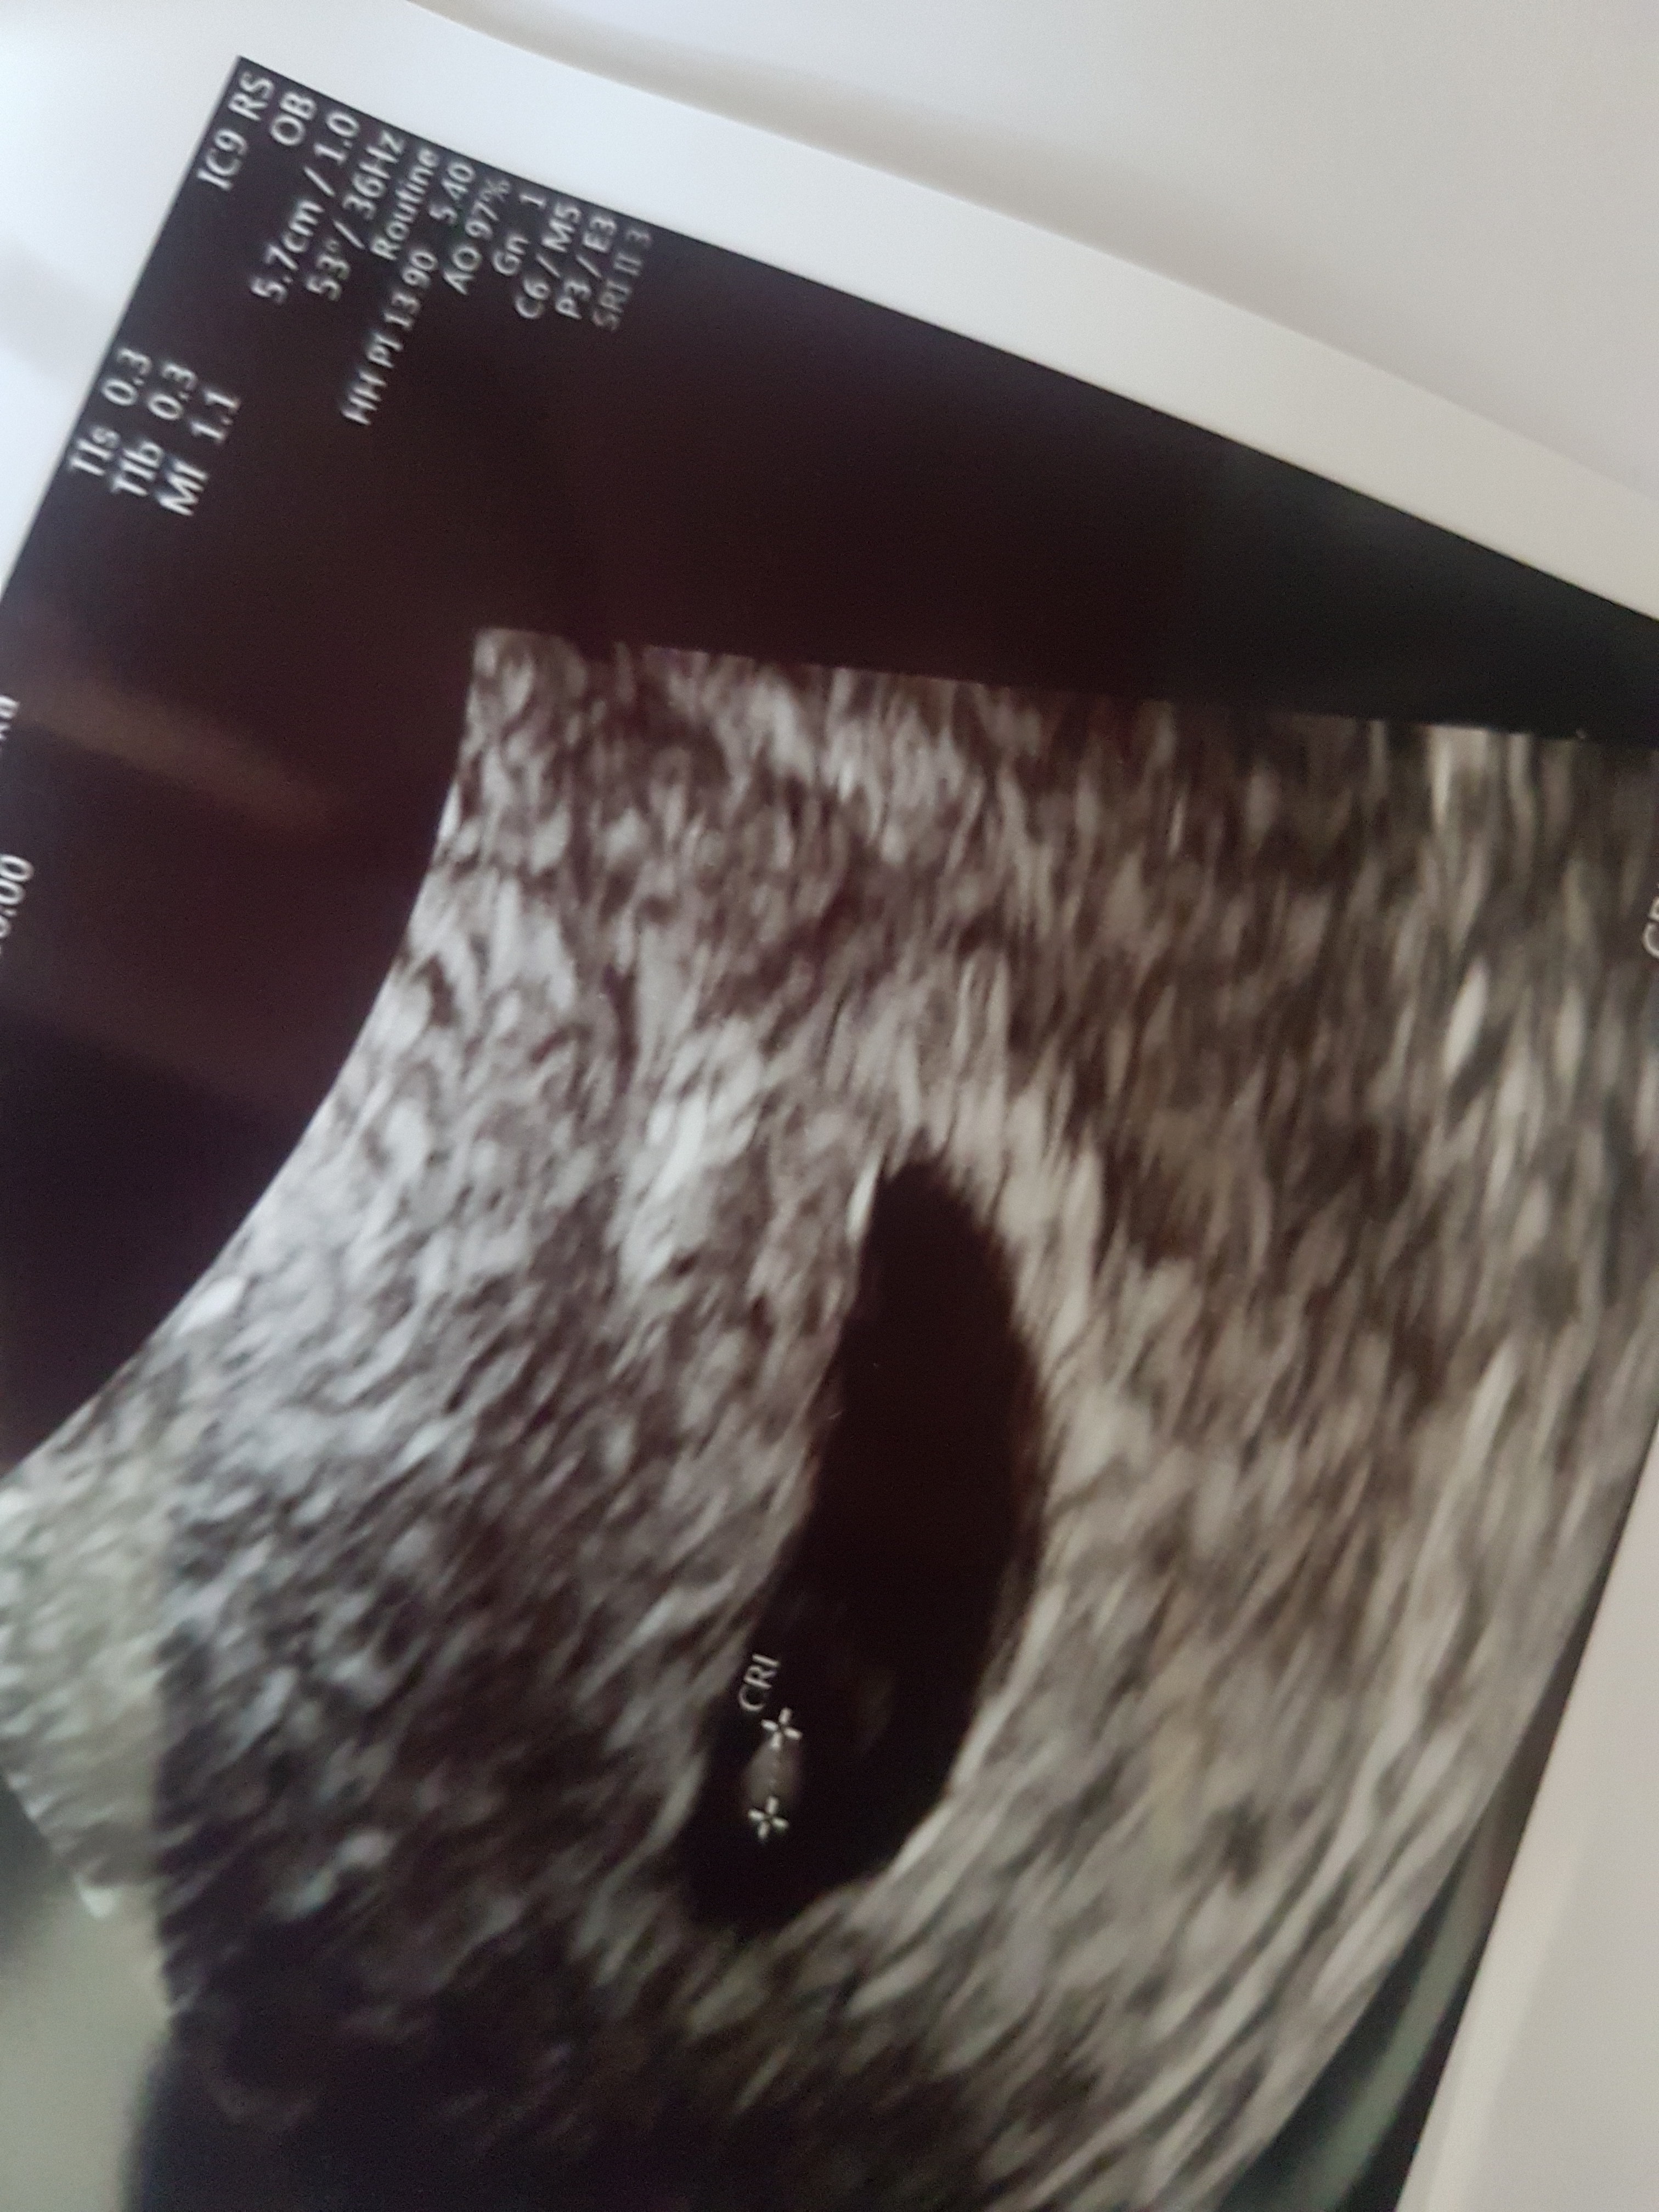

Zaczynam swoja przygodę z ciążą. To moja pierwsza ciąża, wiec pewnie bede miala sporo pytan do Was. Aplikacje wyliczaja mi termin na ok 15.01. Wczoraj robiłam bete, 1515, mam nadzieje, ze to dobry wynik. Owulacje mialam ok. 23/24.04 (o okresie nie mowie, bo ost mialam w lutym ;p). Do lekarza jestem umowiona na 22.05 mam nadzieję, że cos tam zobaczy